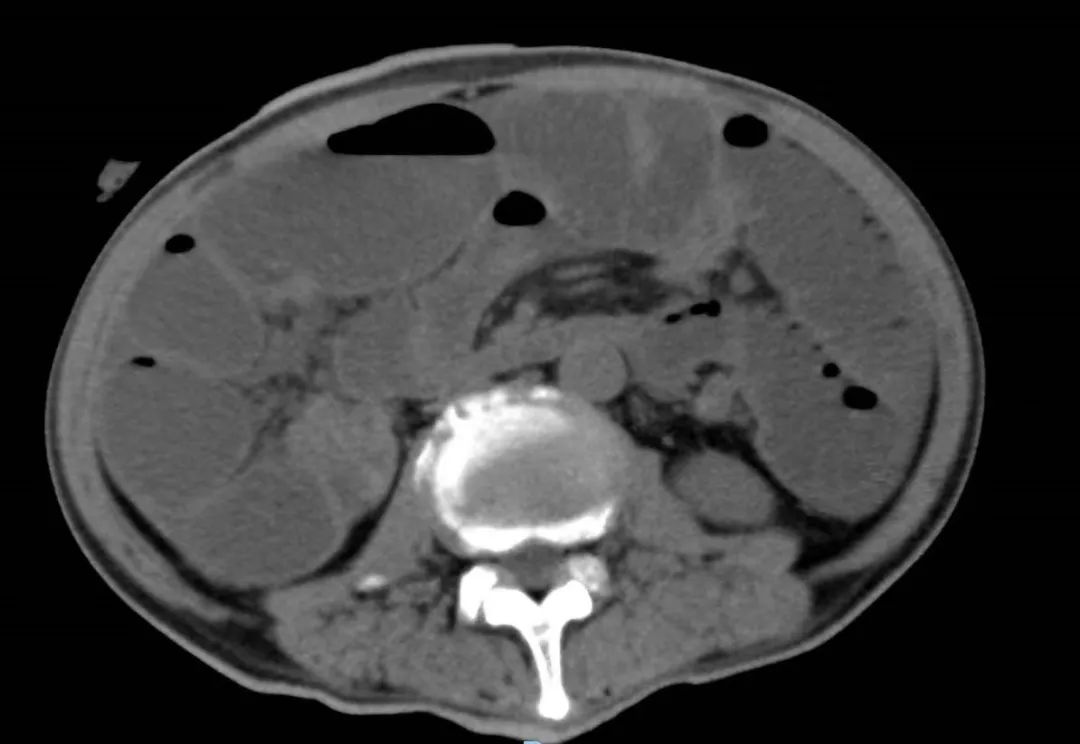

2022年5月的一个凌晨,一位93岁的老奶奶因为腹胀和呕吐被送到了新龙泽院区急诊科,经过问诊和初步查体后,接诊医生考虑患者存在肠梗阻,立即为患者申请了急诊腹部CT检查,结果显示患者的升结肠存在一个巨大的肿物堵塞了肠腔。在给予补液和胃肠减压的同时,普外科立即对患者的病情进行了紧急评估和讨论。肿瘤导致患者出现肠梗阻,手术是唯一的解决方案,但患者高龄且身体非常瘦弱,围手术期发生肺部感染、心脑血管事件等并发症的概率非常高。普外科高鹏骥主任医师制定了急诊实施腹腔镜下右半结肠切除的手术方案,并在麻醉科和手术室医护团队的密切配合下顺利完成了手术。